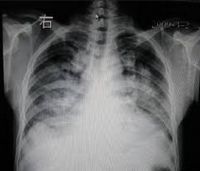

肺水肿间质期的X线表现主要为肺血管纹理模糊,增多,肺门阴影不清,肺透光度降低,肺小叶间隔增宽。两下肺肋膈角区可见与胸膜垂直横向走行的KerleyB线,偶见上肺呈弧形斜向肺门较KerleyB线长的KerleyA线。肺泡水肿主要表现为腺泡状致密阴影,呈不规则相互融合的模糊阴影,弥漫分布或局限于一侧或一叶,或从肺门两侧向外扩展逐渐变淡成典型的蝴蝶状阴影。有时可伴少量胸腔积液。但肺含量增加30%以上才可出现上述表现。CT和核磁共振成像术可定量甚至区分肺充血和肺间质水肿,但费用昂贵。

肺水肿2

• 肺泡实变阴影,早期呈结节状阴影,约0.5-1cm大小,边缘模糊,很快融合成斑片或大片状阴影,有含气支气管影像.密度均匀。

• 分布和形态呈多样性,可呈中央型、弥漫型和局限型。中央型表现为两肺中内带对称分布的大片状阴影,肺门区密度较高,形如蝶翼称为蝶翼征。局限型可见于一侧或一叶,多见于右侧。除片状阴影外,还可呈一个或数个较大的圆形阴影,轮廓清楚酷似肿瘤

• 动态变化:肺水肿最初发生在肺下部、内侧及后部,很快向肺上部、外侧及前部发展,病变常在数小时内有显著变化。

• 胸腔积液:较常见,多为少量积液,呈双侧性。

• 心影增大。